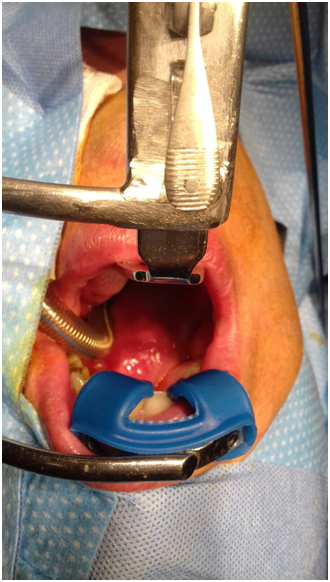

A 42 year old male, with no previous medical history was referred to the Otorhinolaryngology and Head & Neck surgery outpatients’ department at Mater Dei Hospital with Obstructive Sleep Apnoea (OSA) symptoms. The patient admitted to a few year history of such symptoms. During examination, a large right sided lesion was seen in the oropharynx which seemed to be arising from the soft palate. This lesion was seen to be crossing the midline and most likely contributing to his obstructive symptoms. The patient underwent a flexible nasoendoscopy which showed a large lesion extending to the lateral nasal cavity. Subsequently the patient underwent urgent imaging with computed tomography (CT) (Figure 1) of the neck and thorax which showed a large mass with the most likely site of origin being in the right tonsillar bed. A dedicated magnetic resonance imaging (MRI) (Figure 2) (Figure 3) of the neck was recommended for staging, to better assess the extent of the lesion. Two hypoechoic intrahe-patic liver lesions were discovered were also noted. A biopsy of the lesion arising from soft palate was taken under local anaesthesia which was reported as adenomatoid acinar hyper-plasia.

Figure 1 Coronal CT scan showing a large right sided soft tissue swelling causing almost complete obstruction of the upper airway.